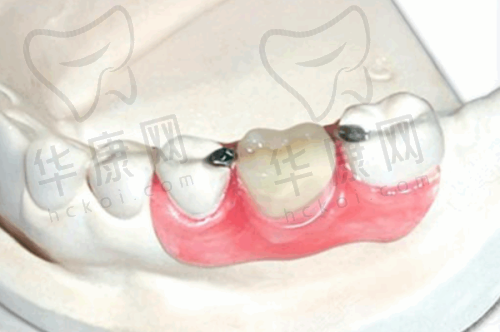

北京美冠塔口腔医院的口腔修复项目参考金额为3000元,预计修复时间为90天。在这个价格区间内,医院凭借其专精的医生团队和精良的技术,为患者提供高质量的口腔修复服务。医生们会根据患者的具体口腔状况,制定个性化的修复方案,确保修复成效达到至佳。而且医院使用的都是优质的材料,在确保修复成效的同时,也保护了患者的口腔健康。